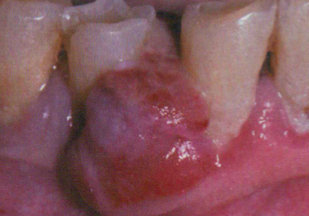

Peripheral Giant Cell Granuloma